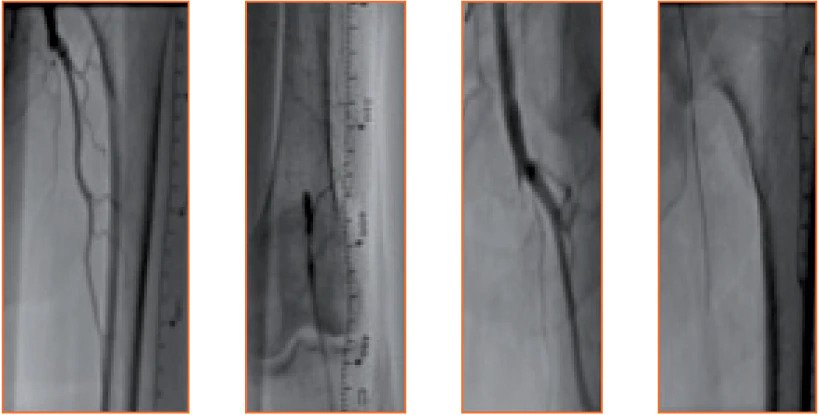

64-year-old male patient presented with left-sided CLI. Over the preceding four months the patient experienced left-sided rest pain and despite receiving best medical treatment, developed a dry, non-healing ulcer of the toe. Puncture of the right groin and cross-over approach, demonstrated a very long, 31 cm, TASC D, femoropopliteal CTO on angiogram. The SFA occlusion was recanalized with a wire intraluminally, followed by 3 passes of a 6F Rotarex S™ Atherectomy Catheter, after which 3 PTAs resulted in a completely restored flow. The patient remained asymptomatic after 18 months.

<h3>Before treatment, Flush occlusion of left SFA to PII segment. Crossed intraluminally with guidewire.</h3>

Before treatment, Flush occlusion of left SFA to PII segment. Crossed intraluminally with guidewire.

<h3>Extensive collaterals of SFA reconstituting at PII segment, with 2 vessel run-off BTK.</h3>

Extensive collaterals of SFA reconstituting at PII segment, with 2 vessel run-off BTK.

<h3>Angiogram after 1 and 3 passes with Rotarex™ Atherectomy Catheter.</h3>

Angiogram after 1 and 3 passes with Rotarex™ Atherectomy Catheter.

<h3>Final angiogram showing restored flow in SFA and 3 vessel run-off BTK.</h3>

Final angiogram showing restored flow in SFA and 3 vessel run-off BTK.